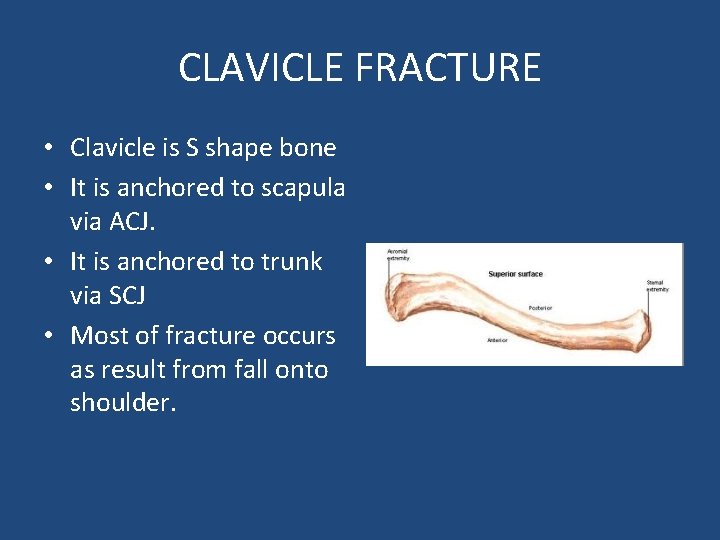

CLAVICLE FRACTURE • Clavicle is S shape bone • It is anchored to scapula via ACJ. • It is anchored to trunk via SCJ • Most of fracture occurs as result from fall onto shoulder.